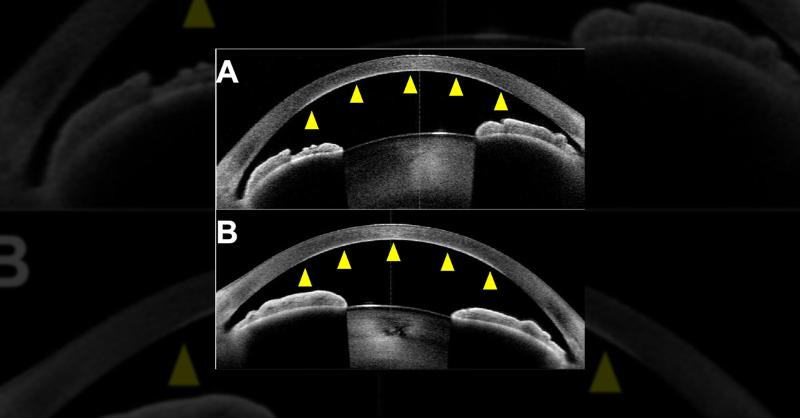

An 84-year-old man with gradually progressing corneal opacity was referred to the hospital. The patient had initially presented with corneal opacity five years ago. His medical history included type two diabetes mellitus, hyperuricemia, cholangiocarcinoma following pancreatoduodenectomy, and chronic lymphocytic leukemia (CLL). The patient had previ